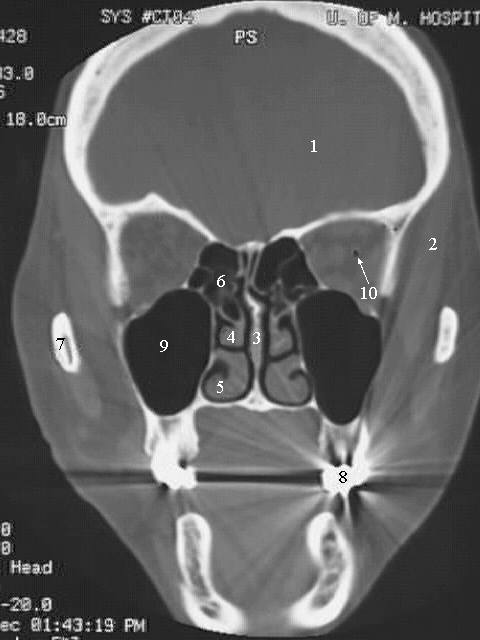

Head & Neck: Head CT Coronal:

1. Brain

2. Temporalis Muscle

3. Nasal Septum

4. Middle Concha

5. Inferior Concha

6. Ethmoid Air Sinus

7. Mandible

8. Tooth with metal filling (artifact)

9. Maxillary Air Sinus

10. Eyeball